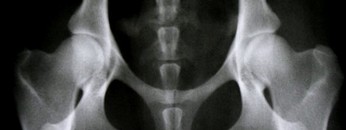

B - stawy biodrowe prawie normalne i bardzo nieznaczne odchylenie od normy, ale pozwalające na rozpoznanie schorzenia

B - stawy biodrowe prawie normalne i bardzo nieznaczne odchylenie od normy, ale pozwalające na rozpoznanie schorzenia.